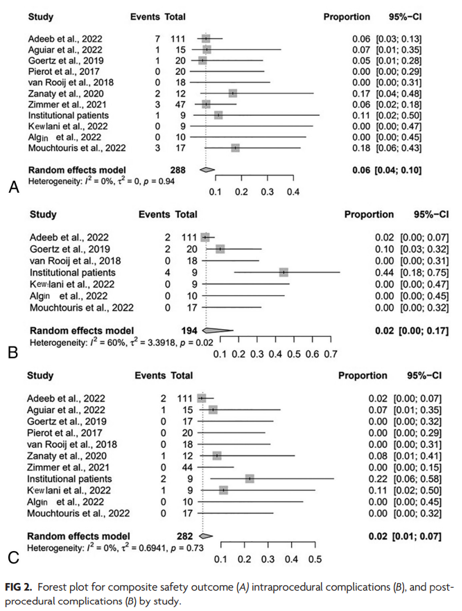

复合安全性结局(composite safety outcome)为8%(95% CI,3%-17%;I2=34%),术中并发症发生率为6%(图2B);血栓栓塞并发症为2%,出血性并发症为1%,装置放置问题1%,血管夹层发生率1%。术后并发症发生率为1%,全因死亡率为2%(95% CI,1%-7%;I2=0%)。